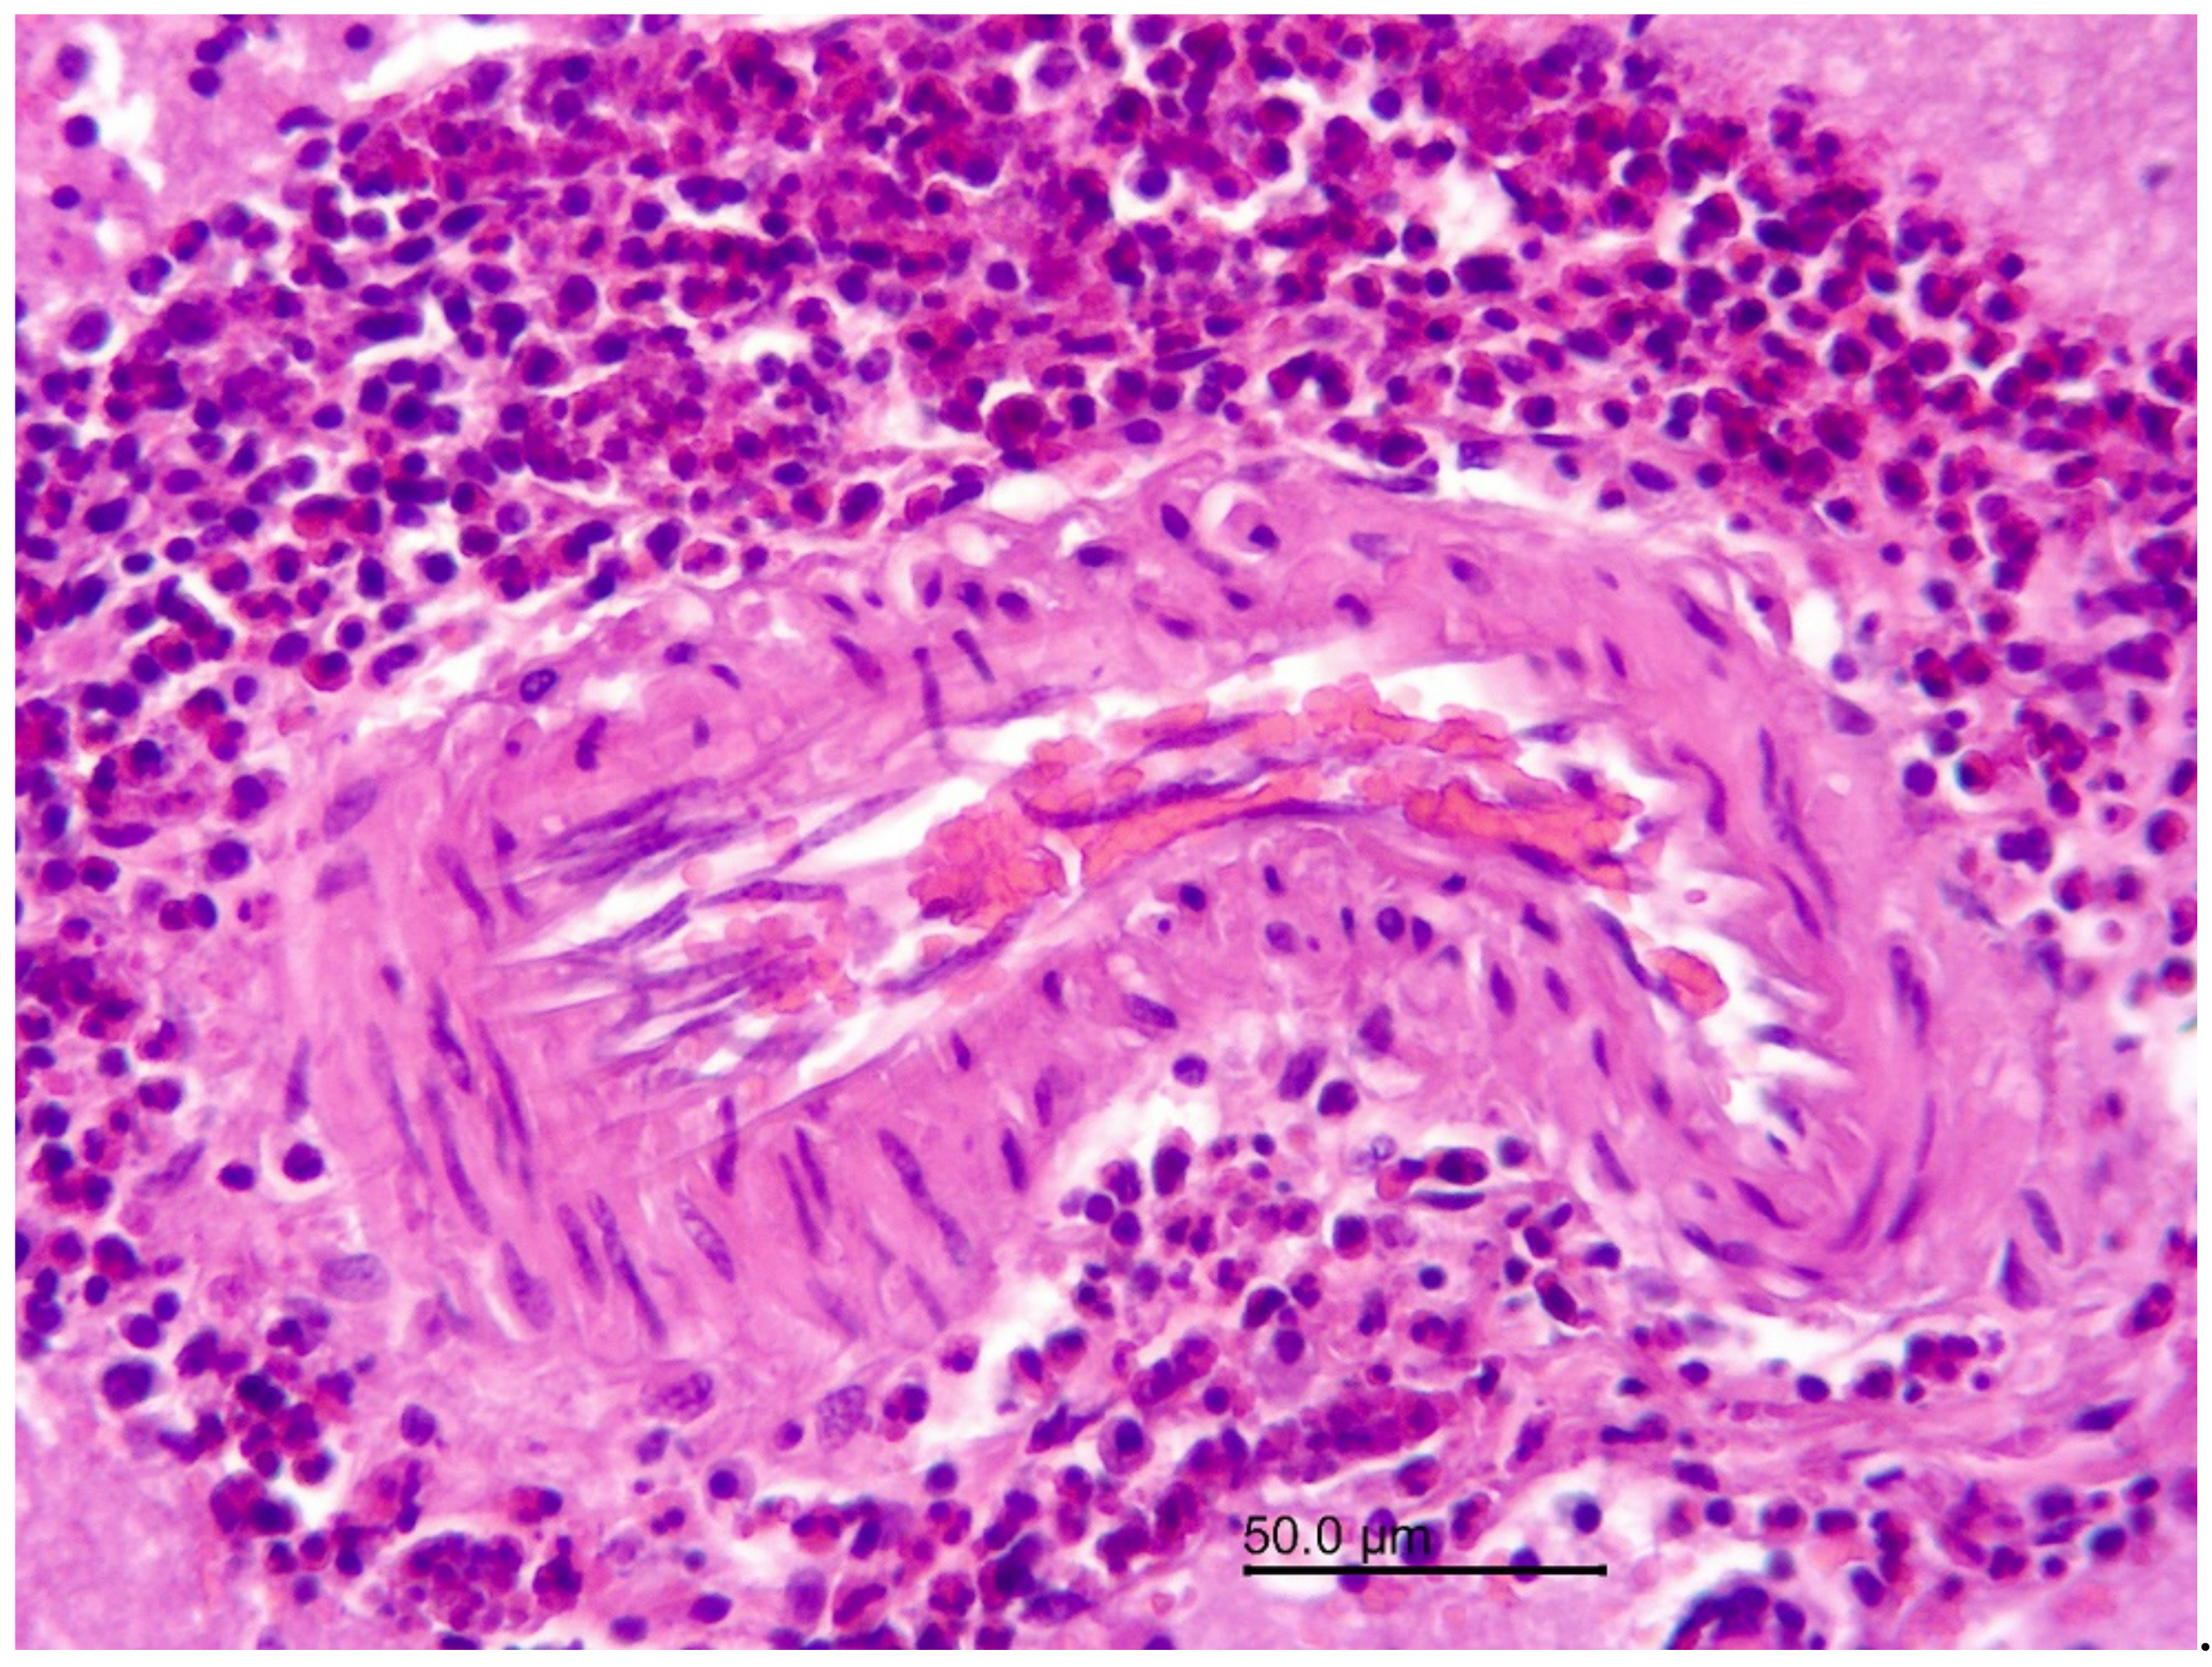

3.1.2. Necropsy and Histopathology

3.2.1. Necropsy and Histopathology